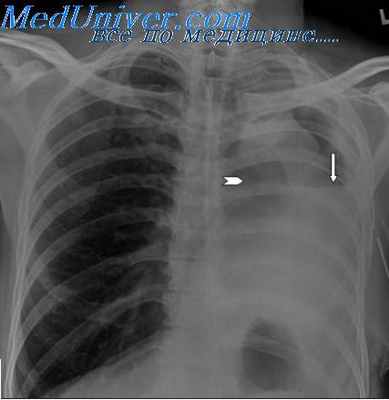

Заключение. Рентгенологические методы визуализации являются “золотым стандартом” в диагностике эмпиемы плевры на фоне БПС. Дифференциальный подход, основанный на оценке факторов риска (этиология эмпиемы, длина культи главного бронха, диаметр бронхоплеврального соустья и исходное состояние остаточной плевральной полости), позволяет добиться снижения летальности и частоты рецидивов у пациентов с БПС.

При сравнительном анализе частоты бронхо-плевральных свищей в зависимости от оставления культи главного бронха (первая группа) или же его полной ампутации (вторая группа) выявилась четкая закономерность, носившая высокодостоверный характер. Так, у 79 больных первой группы бронхо-плевральные свищи возникли после 13 операций, чго составило 16,4%. При этом справа они возникли у 6 (20,0%) и слева — у 7 больных (14,2%). Это совпадает или незначительно превышает усредненные данные публикаций большинства торакальных хирургов.

После 331 операции во второй группе бронхо-плевральные свищи осложнили течение послеоперационного периода у 5 больных, что составило 1,5%. При этом справа они возникли у 4 (3,6%) и слева — у 1 больного (0,4%). Таким образом применение методики полной ампутации главного бронха с плевризацией дефекта в средостении позволило снизить частоту формирования бронхо-плевральных свищей в послеоперационном периоде в 10 и более раз.